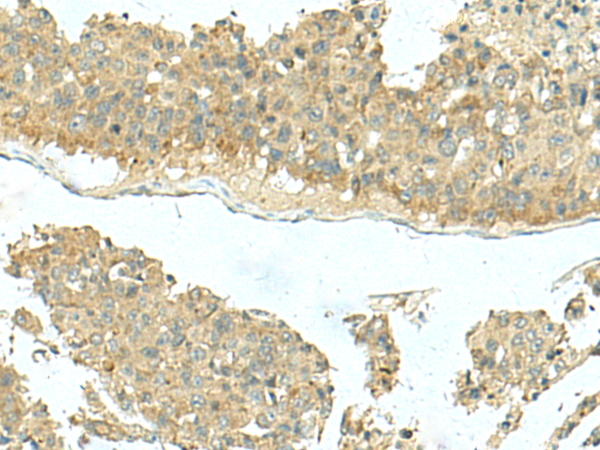

IHC positive control:

IHC Recommend dilution:

40-200